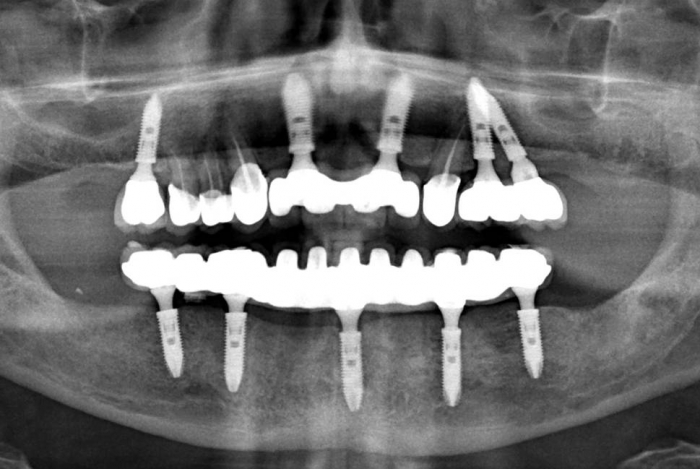

Raio X final com próteses fixas instaladas